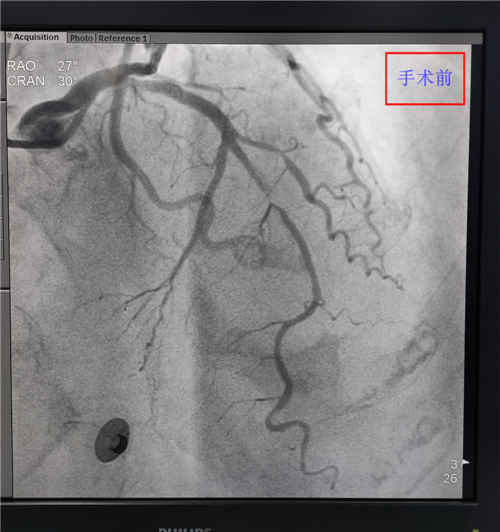

內(nèi)二科成功開展首例急診PCI手術(shù)

? ? ? ?4月19日,我院介入手術(shù)治療團(tuán)隊成功開展了羅江區(qū)首例急診PCI手術(shù)。此次手術(shù),標(biāo)志著我院介入治療技術(shù)更加成熟。

? ? ? ?患者80歲,胸痛2小時于4月19日來我院就診,急診科胸痛中心考慮診斷急性廣泛前壁ST段抬高型心肌梗死,病情危重。經(jīng)與家屬溝通后,我院介入手術(shù)治療團(tuán)隊為患者行急診PCI手術(shù),手術(shù)歷時1個多小時,術(shù)后患者胸痛癥狀明顯改善,恢復(fù)較好。